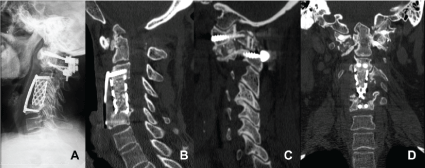

Computerized Tomography (CT) with sagittal and coronal reconstruction has been further used in initial evaluation of RA of CVJ, in preoperative planning, and post-operatory follow-up, providing a better bone visualization in comparison to Nuclear Magnetic Ressonance (NMR) and radiographs. The case illustrated below is of a patient with RA of CVJ, where the subject radiographic imaging didn't contribute for the diagnosis, but CT clearly showed atlantoaxial instability associated to basilar invagination (Figure 1). NMR is the best exam to evaluate soft tissues and neural elements, helping to trace the actual available space for spinal cord, the magnitude of pannus and the extent of soft parts destruction. This is an important matter because, in addition to bone compression, the pannus reduces even further the available space for the cord within vertebral canal. Dvorak, et al. [18] show that two thirds of rheumatoid patients with atlantoaxial subluxation have a pannus diameter over 3 mm (0.12 in), and recommend surgical treatment for those with Space Available for the Cord (SAC) < 6 mm. Basilar invagination may be measured in MRI through the Cervicobulbar Angle (CBA), which is measured by two lines tangent to the anterior faces of the bulb and cervical cord. Normal CBA ranges from 135° to 175°. Values lower than 135° are related to the odontoid vertical migration and are associated to myelopathy [19].

Figure 1: Lateral view radiography (A) of a patient with RA of CVJ, showing the difficulty to visualize CVJ. The diagnosis of pathologies in this region in simple radiographs might be difficult. CT with sagittal reconstruction (B) of the same patient, clearly showing the presence of atlantoaxial instability associated to basilar invagination. View Figure 1